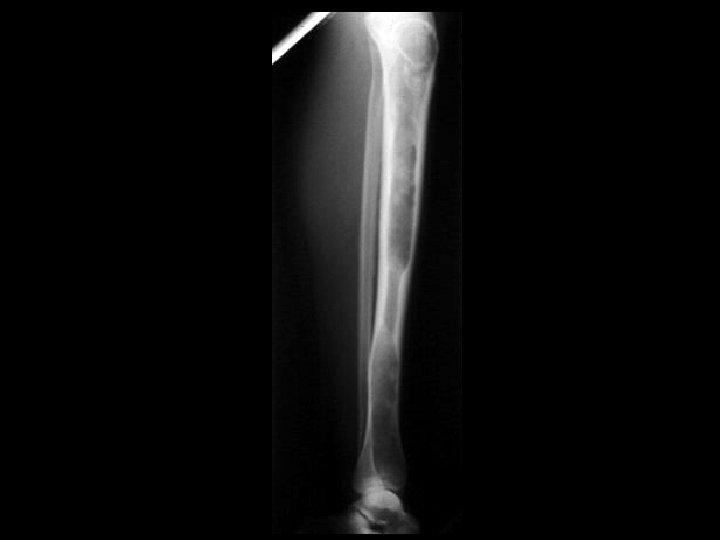

Fibrous dysplasia • Findings: – Long lytic lesion in a long bone – Cortical thickening – “ground glass matrix” • ddx: – NONE! – This is an Aunt Minnie!